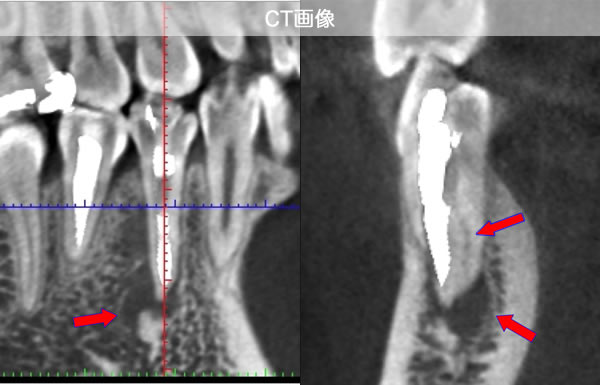

CT画像を見ると根管が2本あることが分かりました。(レントゲンだけでは分かりませんでした。)

| 治療説明 | 右下第2小臼歯、他院で根管治療した後に頬側根尖部から排膿があます。X線CT画像では、根管が2本あり、そのうち舌側が根管充填されていませんでした。顕微鏡下で2根管とも根管充填処置を行い、4ヶ月で、X線透過像は消失しました。 |